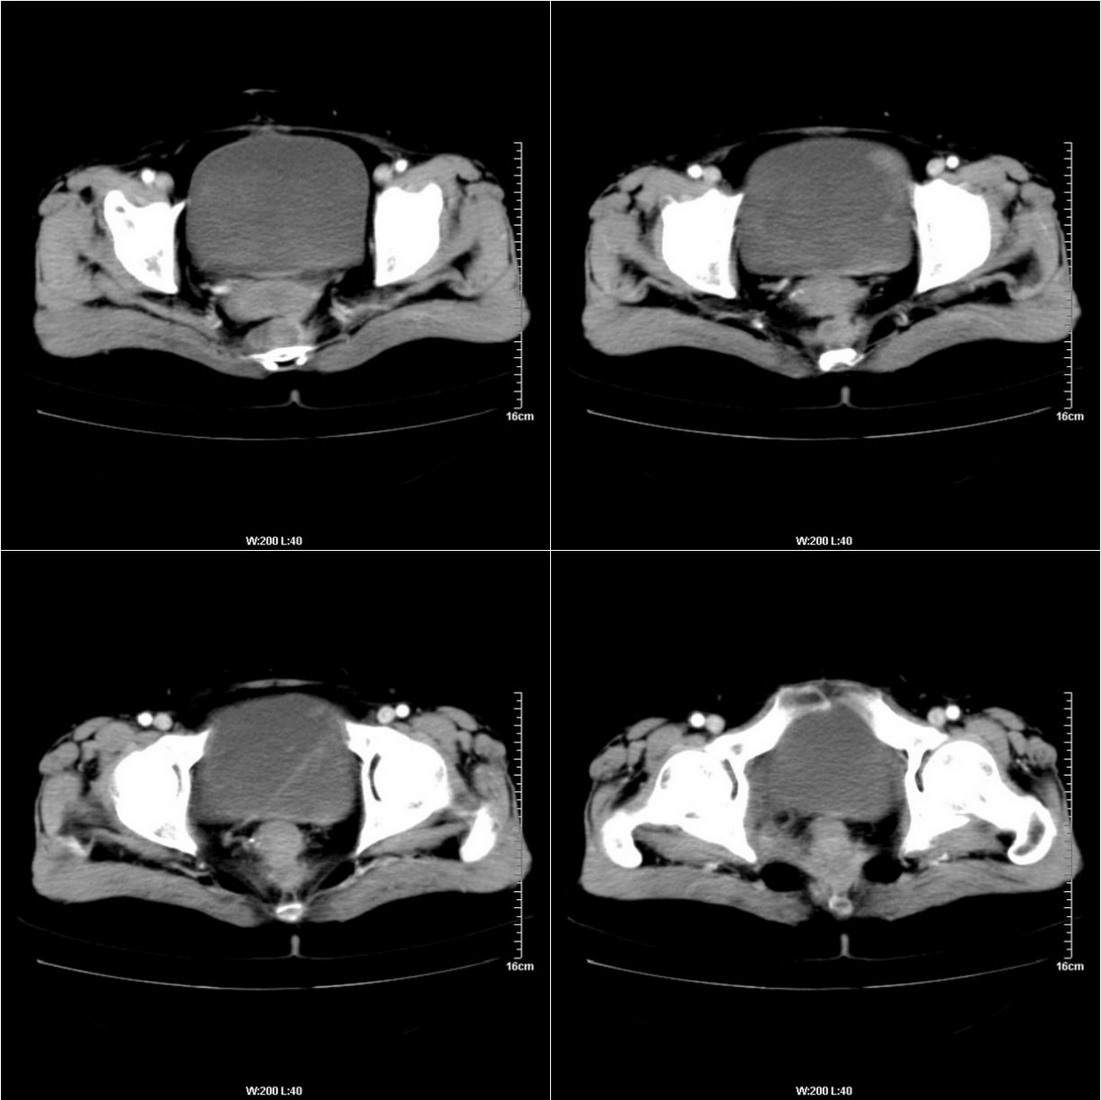

不知道病人的直肠癌手术方式如何,直肠已经全部切除,乙状结肠造瘘于左下腹,肛门应该也没有保留吧?如此,应该是复发了:

病变于肛尾韧带、右侧坐骨肛门窝内并顺右侧肛提肌向右侧闭孔内肌蔓延,骶前软组织内也形成了肿块,麻烦啊!

典型直肠癌术后骶骨前转移复发.

膀胱壁见索条状软组织密度影伴强化,可考虑炎性肉芽肿样增生改变,常见于放疗后或慢性感染;直肠及周围软组织见肿块,轻度强化,考虑直肠癌术后复发,并侵犯周围组织